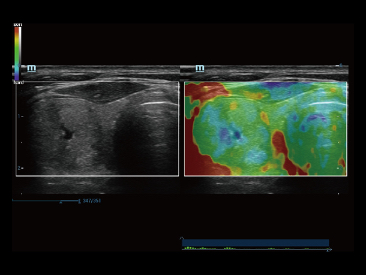

Sejak didirikan, Mindray terus mencari cara baru untuk meningkatkan keandalan diagnostik. Didukung Teknologi ZONE Sonography? terkini, platform ZST+ baru Resona 7 meningkatkan kualitas gambar ultrasound melalui pengambilan zona dan pemrosesan data saluran.

Selain kualitas gambar premium, Resona 7 juga meningkatkan kemampuan penelitian klinis dengan V Flow revolusioner untuk evaluasi hemodinamika vaskular, serta pengambilan penampang tercanggih dari rangkaian data 3D untuk diagnosis CNS pada janin. Kombinasi pengoperasian multisentuh berbasis gerakan yang paling intuitif dengan semua fitur klinis penting membuat Resona 7 menjadi gebrakan baru dalam inovasi ultrasound.